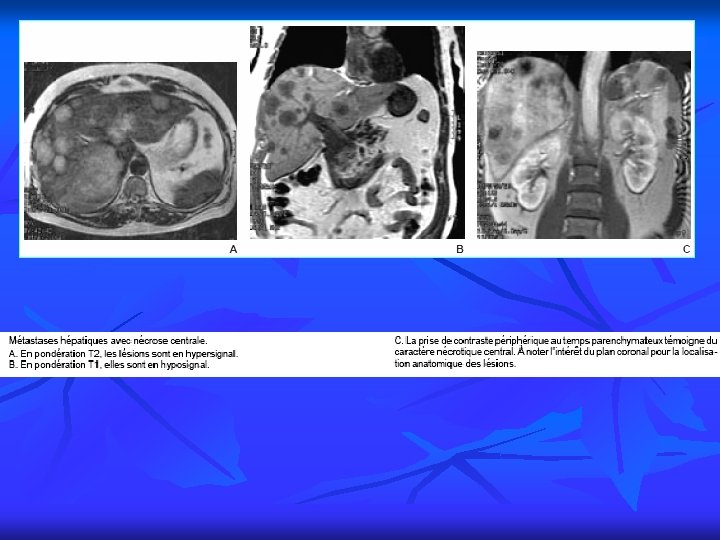

PRINCIPALES INDICATIONS 12 4. Imagerie du foie, des voies biliaires et du pancréas n Pathologie du foie Tumeurs bénignes Tumeurs malignes Cirrhose